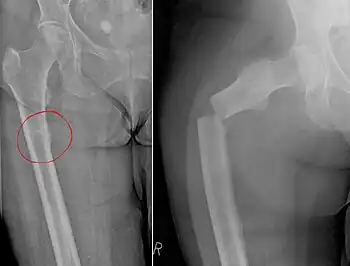

| Chalkstick fracture due to bone metastasis of breast cancer. Left image shows the metastasis, on the right a pathological fracture a few days later. | |

Chalkstick fractures are fractures, typically of long bones, in which the fracture is transverse to the long axis of the bone, like a broken stick of chalk.[1] A healthy long bone typically breaks like a hard woody stick as the collagen in the matrix adds remarkable flexibility to the mineral and the energy can run up and down the growth rings of bone. The bones of children will even follow a greenstick fracture pattern.

Chalkstick fractures are particularly common in Paget's disease of bone, and osteopetrosis.[2] It is also seen in cases of fused spine as in a patient with ankylosing spondylitis.[3]